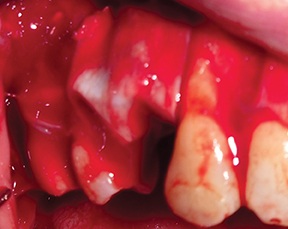

After a four-month healing period, a full-thickness flap was raised to evaluate the outcome (Fig. 21).

Fig. 21: Full-thickness flap raised at surgical re-entry